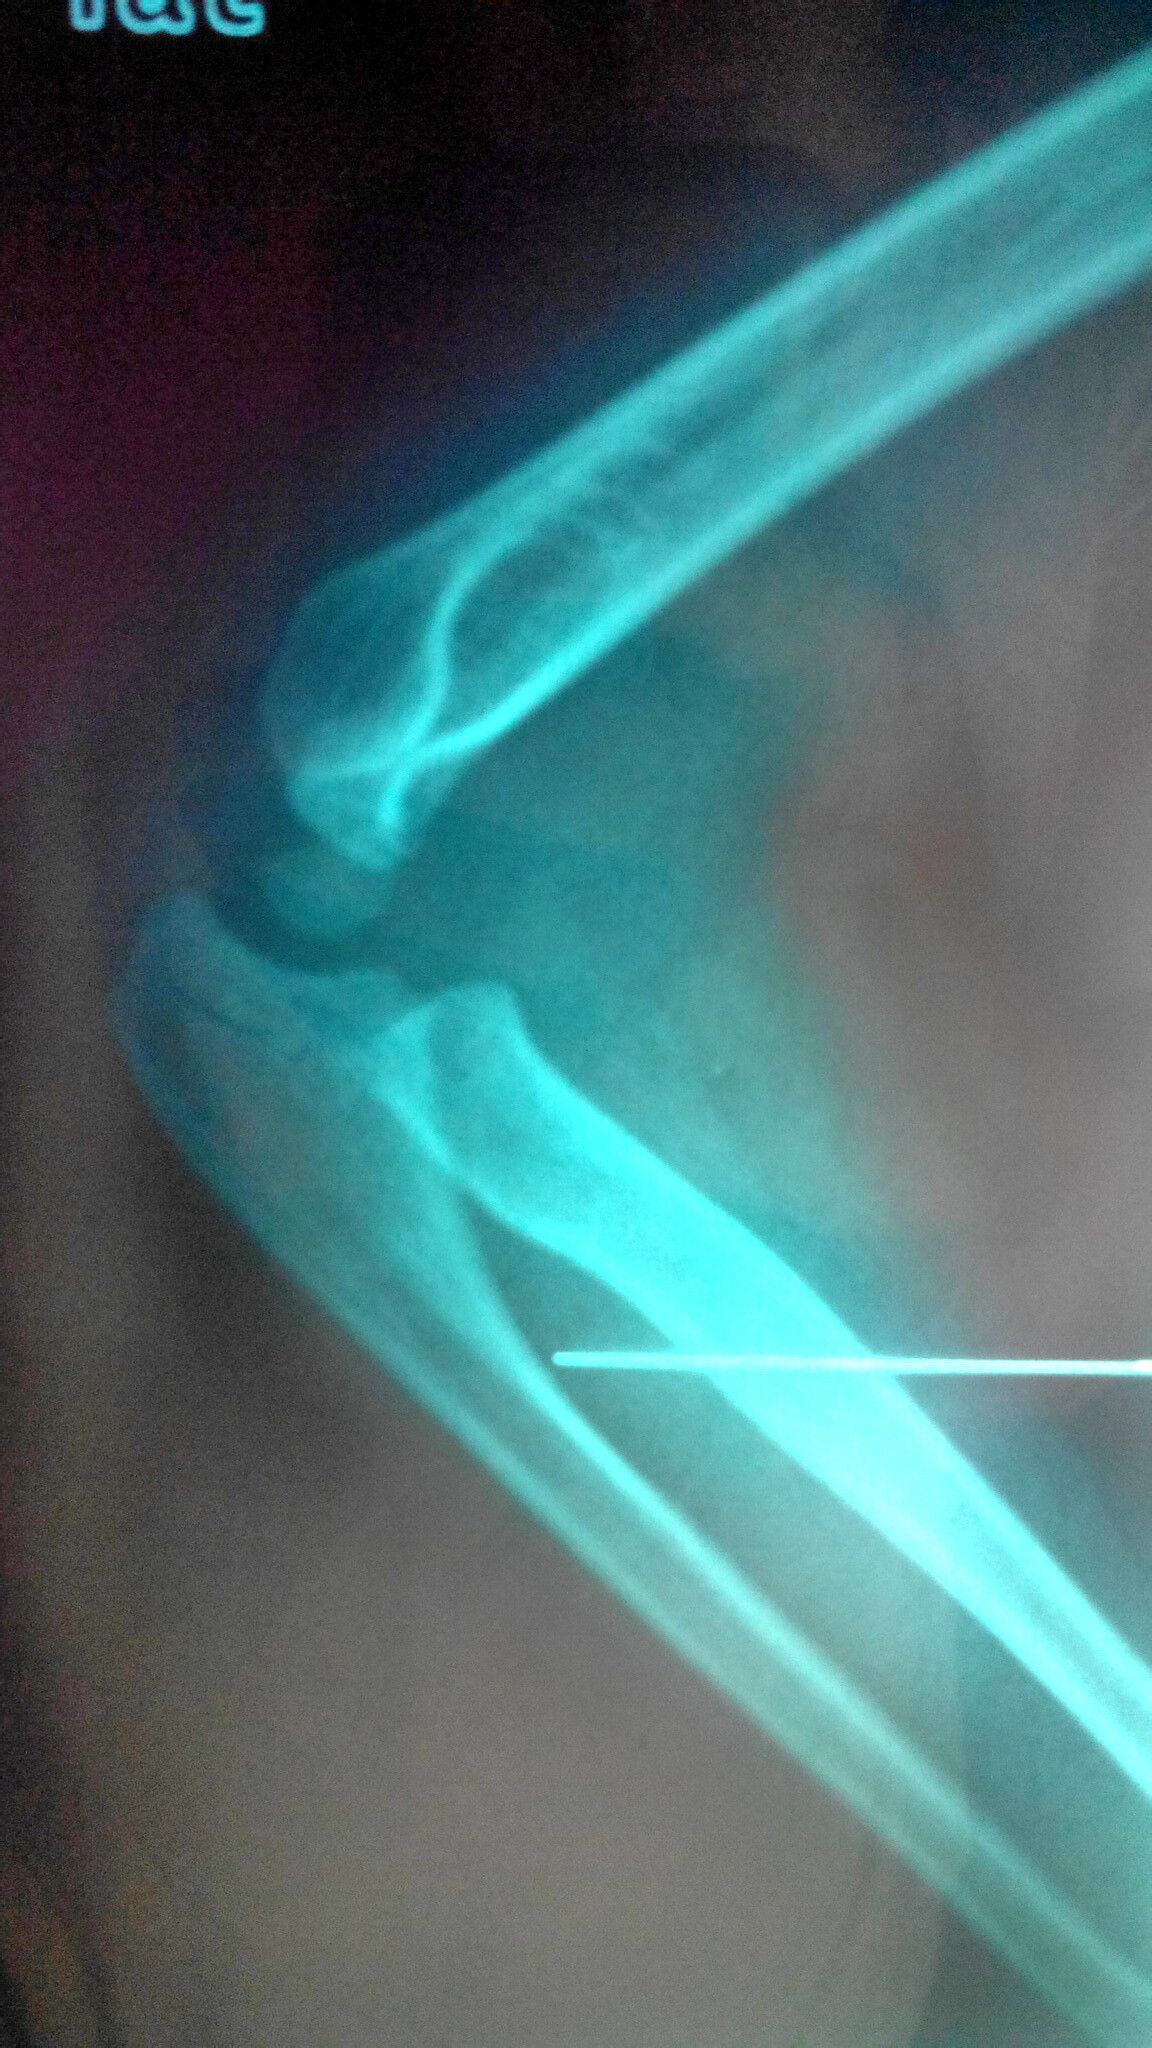

这个算中等程度的严重程度,有骨折自然是不轻的,但是小孩子的骨折一般都是青枝骨折,也就是像柳树枝一样,虽然是有点断,但是外面的树皮,人也就是骨膜把骨头仍然连在一起,所以一般不需要做手术治疗,复位固定好了后,小孩子生长修复很快,恢复也是比较快的。